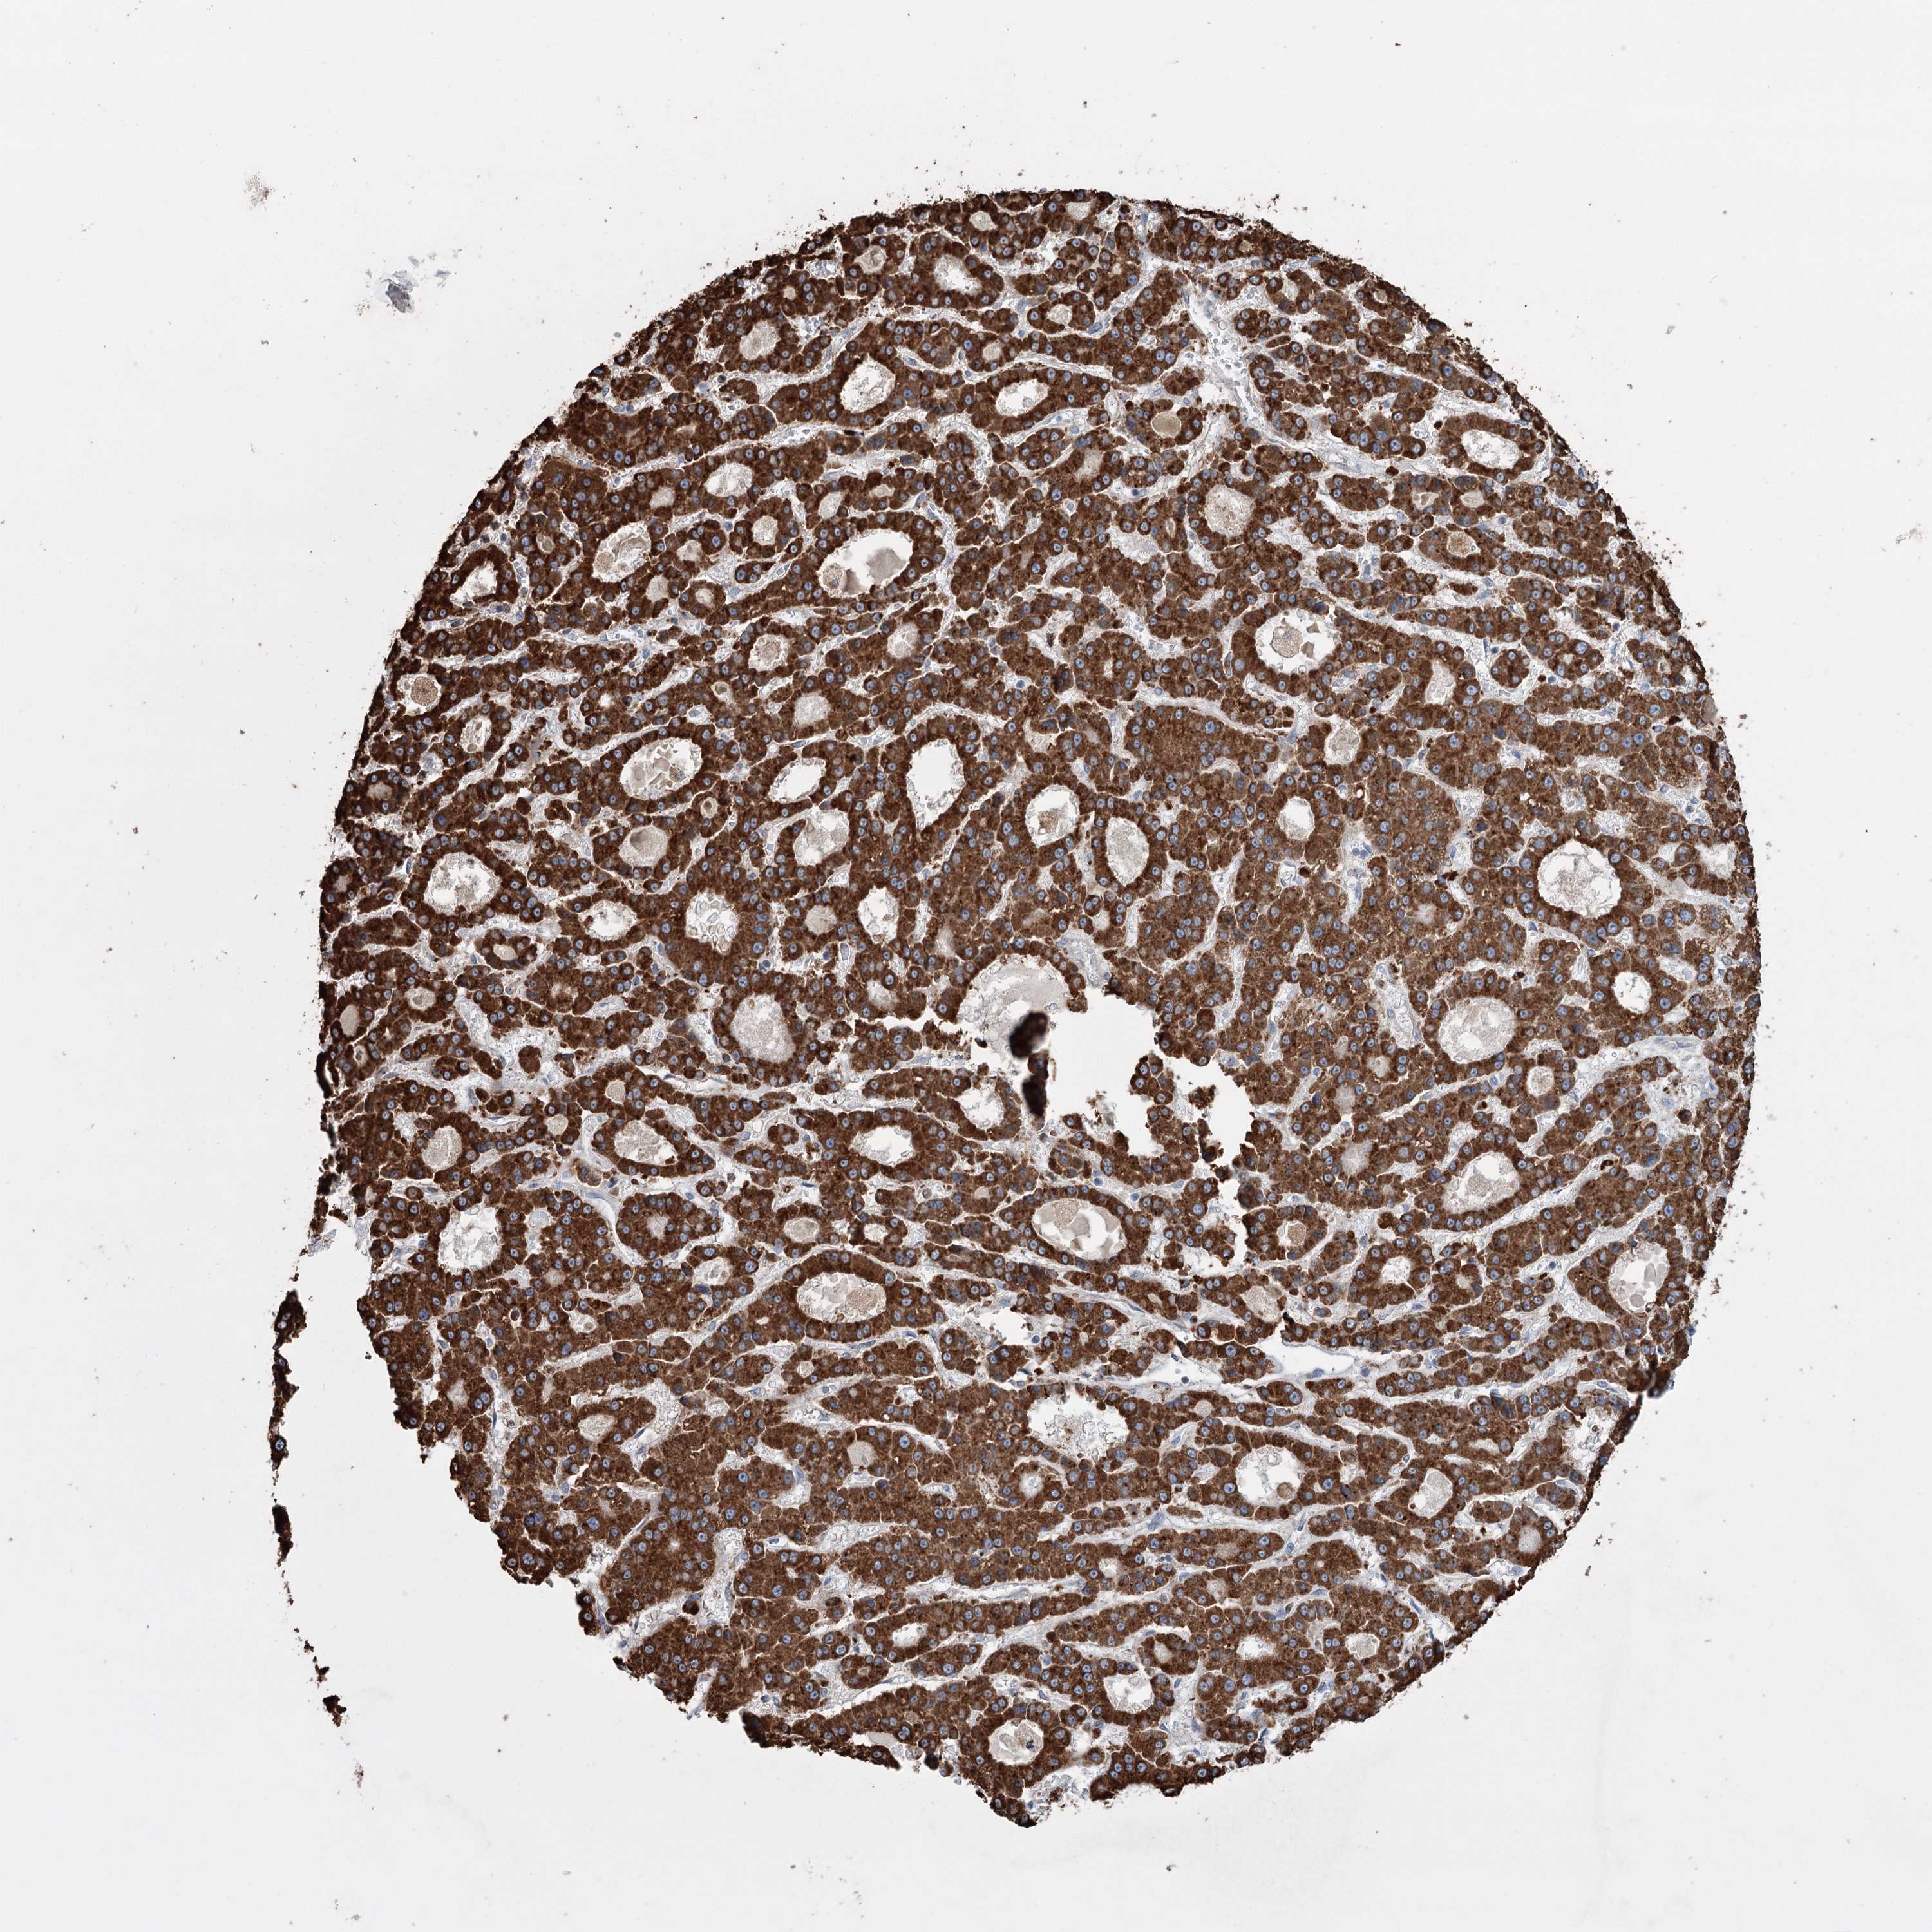

LIVER CANCER - Protein expressioni

A mouse-over function shows sample information and annotation data. Click on an image to view it in a full screen mode. Samples can be filtered based on level of antibody staining by selecting one or several of the following categories: high, medium, low and not detected. The assay and annotation is described here.

Note that samples used for immunohistochemistry by the Human Protein Atlas do not correspond to samples in the TCGA dataset.

Antibody stainingi

Antibody staining in the annotated cell types in the current human tissue is reported as not detected, low, medium, or high, based on conventional immunohistochemistry profiling in selected tissues. This score is based on the combination of the staining intensity and fraction of stained cells.

Each image is clickable and will lead to virtual microscopy that enables deeper exploration of all samples and also displays staining intensity scores, fraction scores and subcellular localization as well as patient and tissue information for each sample.

Antibody HPA038141

Antibody HPA038142

Staining

High

Medium

Low

Not detected

Intensity

Strong

Moderate

Weak

Negative

Quantity

>75%

75%-25%

<25%

None

Location

Nuclear

Cytoplasmic/membranous

Cytoplasmic/membranous,nuclear

Cholangiocarcinoma

Carcinoma, Hepatocellular, NOS